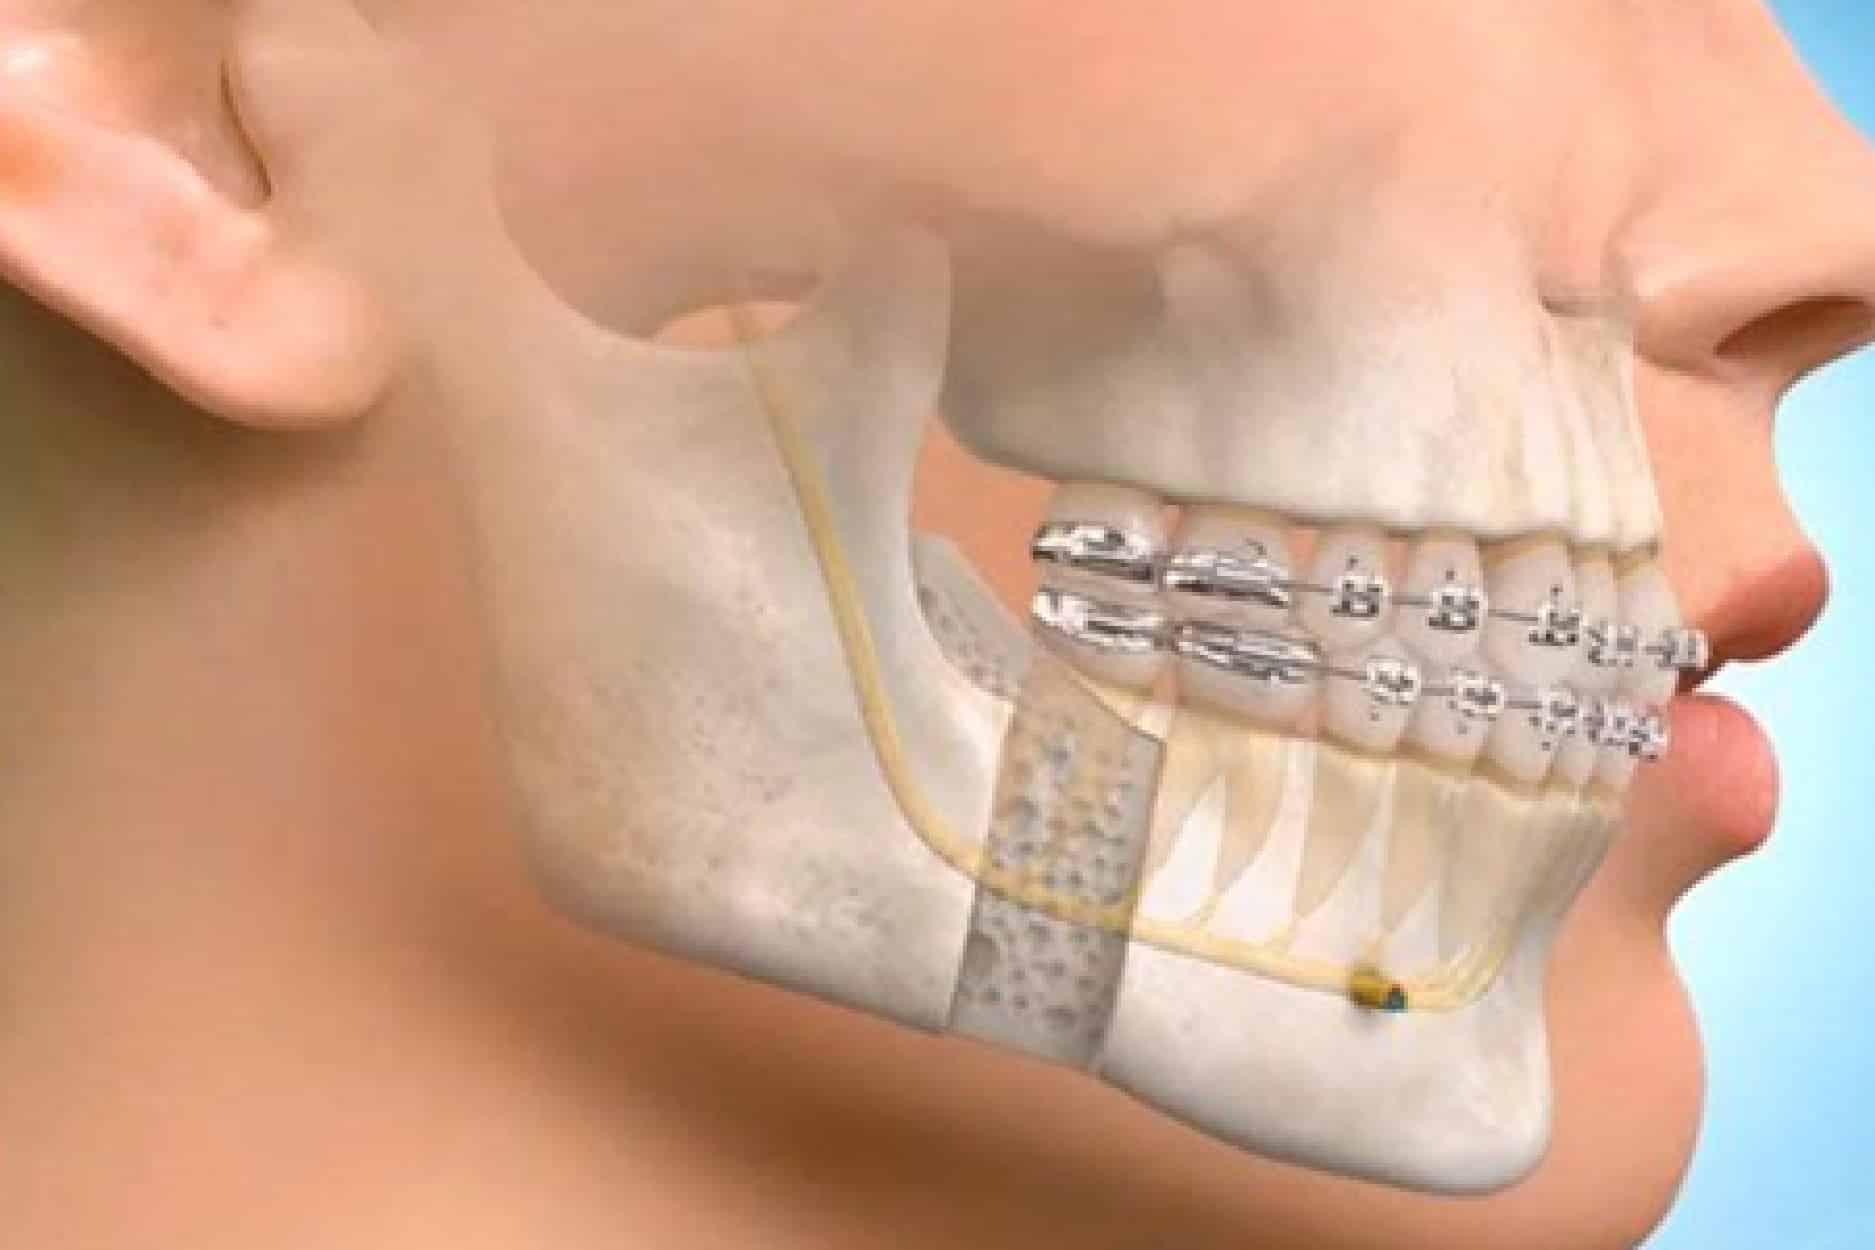

Maxillofacial Surgery

Advanced surgical care for facial trauma, jaw deformities, and oral lesions.